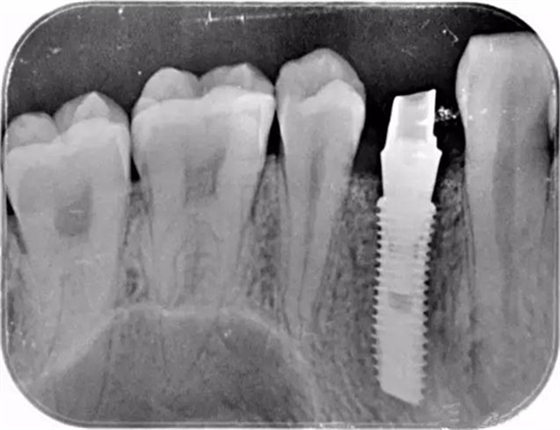

這個是顧客術(shù)后旋入成品基臺的X片

該顧客選擇的是登騰Superline種植體.因?yàn)轭櫩凸歉吖菍挆l件很好,選擇種植4.0*12植體植入。術(shù)中發(fā)現(xiàn)頰側(cè)骨壁存在缺損,植入Biooss骨粉,加固種植體。從照片中可以看到基臺愈合之后的效果不錯。